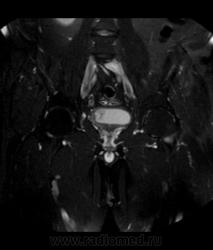

Для динамического контрастирования требуется инъектор, у нас с ним технические неполадки, поэтому контрастное вещество вводим от руки. Но в данном случае четко видно проростание опухолевого компонента через мышечный слой мочевого пузыря, даже некоторой инфильтрацией паравезикальной клетчатки. По гистологии плоско-клеточный рак. У пациента множественные метастазы в легких.